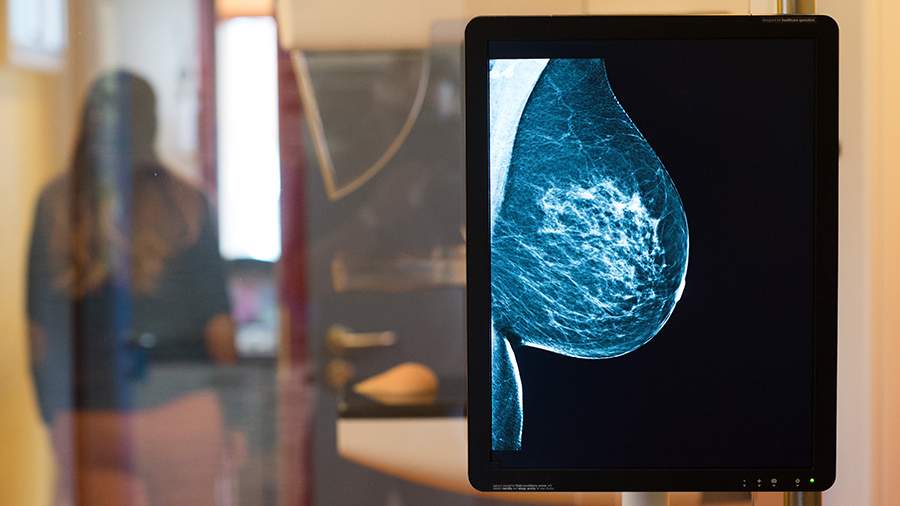

Хотя средний возраст женщин с диагнозом рак молочной железы в России составляет около 61 года, около 10% случаев обнаруживаются у пациенток младше 40 лет. Возможность сохранить фертильность после лечения рассказала 2 октября газете «Известия» гинеколог и эксперт Лаборатории «Гемотест» Ольга Уланкина.

«Рекомендуется самостоятельно осматривать грудь не реже одного раза в месяц. При прощупывании стоит обращать внимание на появление уплотнений в области груди и подмышек, изменения формы груди или сосков, выделения (особенно с кровью) и покраснение кожи. При выявлении этих признаков необходимо обратиться к гинекологу, который проведет осмотр и назначит необходимые исследования. Женщинам до 40 лет рекомендуется ежегодно проходить УЗИ молочных желез, а после 40 — маммографию», — поясняет Уланкина.